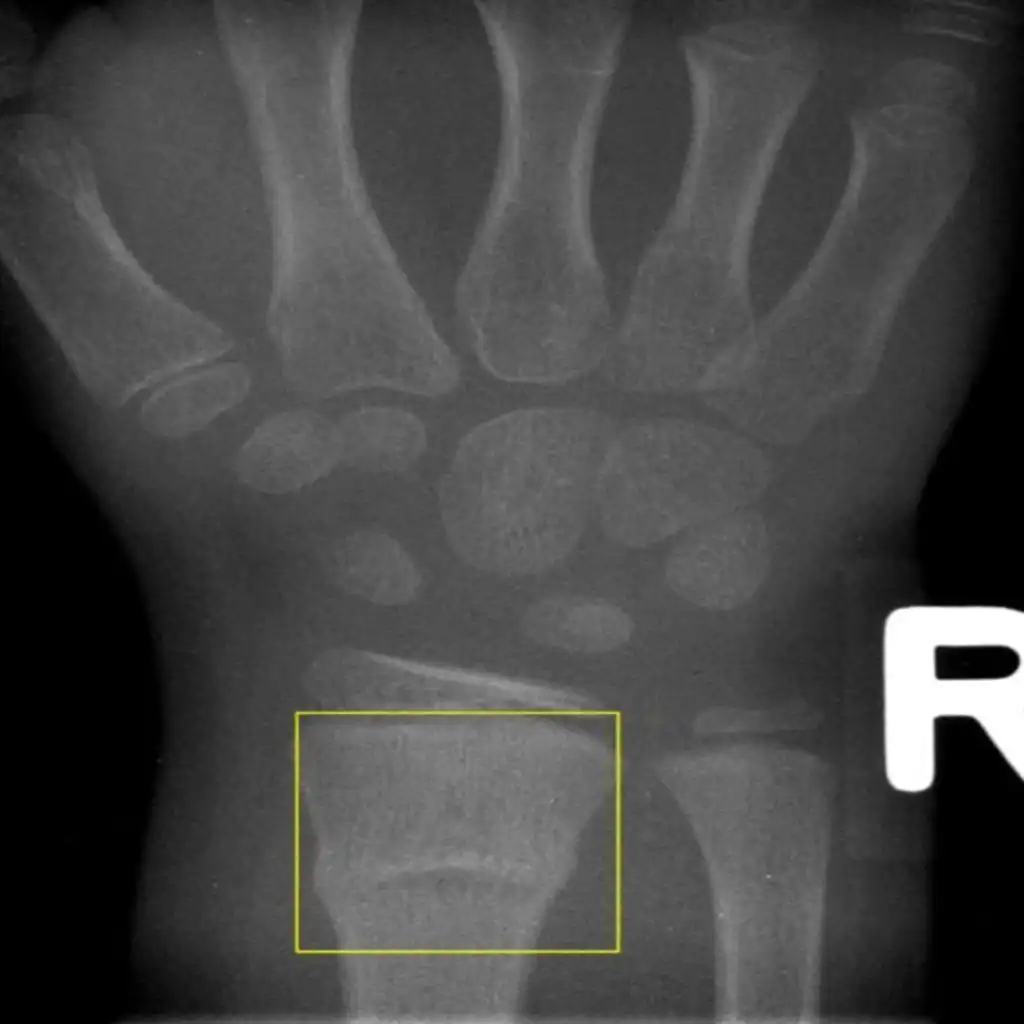

• Torus (Buckle) fractures are a commonly encountered pediatric fracture pattern

• Typically presents as wrist pain secondary to a child falling on outstretched hand

• One edge of the bone “buckles” or bends because children’s bones are softer and more pliable